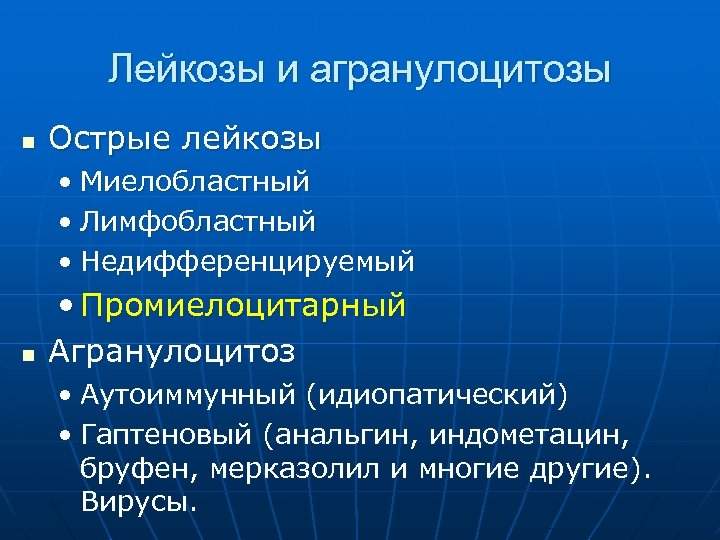

Лейкозы и агранулоцитозы n Острые лейкозы • Миелобластный • Лимфобластный • Недифференцируемый n • Промиелоцитарный Агранулоцитоз • Аутоиммунный (идиопатический) • Гаптеновый (анальгин, индометацин, бруфен, мерказолил и многие другие). Вирусы.